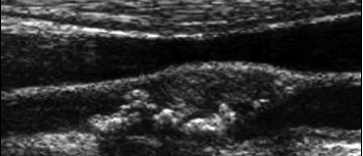

what type of plaqe is this?

smooth CCA plaque

what type of plaque morphology is this?

irregular, complex